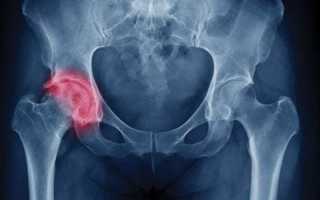

Прежде всего, любой врач должен обратить внимание на симптомы и зафиксировать реакции пациента на простые действия, упомянутые ранее. Таким образом, специалист может выдвинуть предварительный диагноз, после чего он оформляет направление на рентген, чтобы подтвердить или опровергнуть его.

Существуют случаи, когда диагноз не удается установить быстро, и требуется дополнительное обследование, например, компьютерная томография.

С помощью КТ врач может выявить наличие патологических изменений и процессов в области травмы, а также особенности перелома, которые могут затруднить выполнение необходимых лечебных мероприятий.

К сожалению, согласно медицинской статистике, около 25% пациентов, перенесших перелом и выбравших консервативное лечение, сталкиваются с некрозом головки бедренной кости.

Кровоснабжение необходимых участков осуществляется исключительно через артерии, которые начинаются в области тазобедренного сустава. При переломе происходит повреждение этих сосудов, что приводит к тому, что питательные вещества не могут поступать к тканям в достаточном объеме.

В таких случаях сращение сломанной кости происходит за счет соединительной ткани, что не обеспечивает надежного и прочного результата.